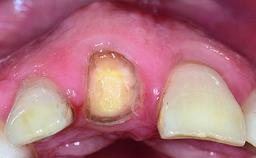

Replacement of a Compromised Upper Right Central Incisor: Hard- and Soft-tissue Augmentation, Late Placement of an RC Bone Level Implant

A 36-year-old male patient with a compromised maxillary central incisor was referred by his general dentist for consultation. The patient’s chief complaints were the gradual debonding of a temporary crown on the right central incisor and unsatisfactory esthetics due to an increasing diastema between the right central and lateral incisors. The patient reported a traumatic event some years previously, when a crown had been placed after root-canal treatment. The referring dentist wanted to provide a new crown restoration, but was concerned about the condition of the residual root. Anamnesis was negative for any other dental or periodontal pathology in the remaining dentition. The patient reported taking no medications: He was a smoker (10 to 15 cigs/day) and had realistic esthetic expectations.

Soft Tissue Anatomy Intact Defective

Bone Volume Horizontally and vertically sufficient Horizontally deficient Deficient vertically or deficient vertically AND horizontally